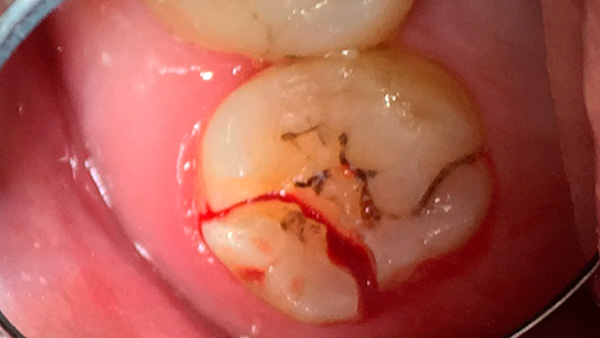

Un esempio di utilizzo di un dente del giudizio conservato come supporto per una protesi di chiusura è mostrato nella foto qui sotto: